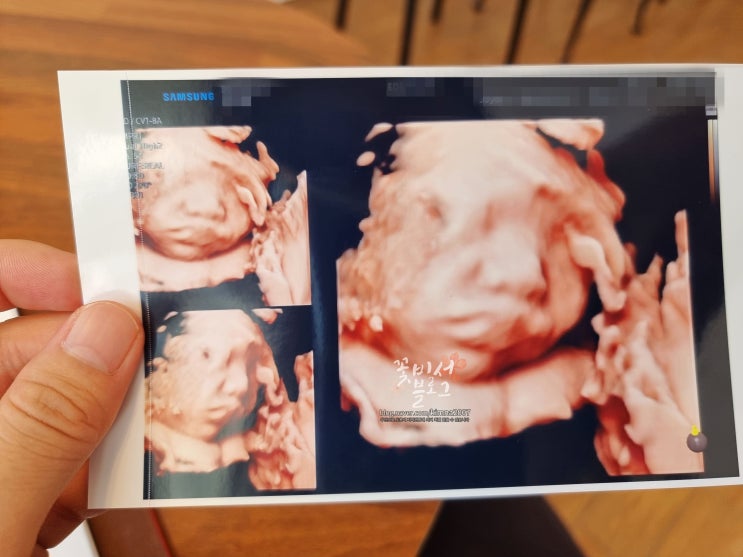

임신 26주 27주 28주 29주 광주 에덴병원 검진 입체초음파 및 산후조리원 예약 후기 육아용품 당근거래 시작

안녕하세요. 꽃비서에요:) 벌써 임신 29주차 8개월 이네요. 시간이 빨리 흘러가는 것 같으면서도 느리게 가...